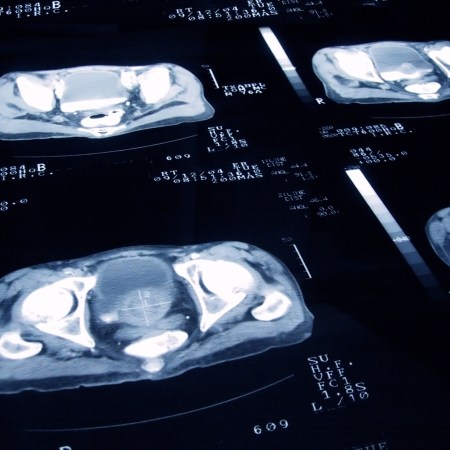

As Nicola Davis reports at The Guardian, a three-year program funded by the nonprofit group Prostate Cancer U.K. is now underway at three hospitals across the country. The Guardian reports that the program will use the ArteraAI Prostate Biopsy Assay system to analyze biopsies from thousands of patients and assess their risk levels and help determine whether a particular drug should be used as part of their treatment.

In an interview earlier this year, ArteraAI’s chief medical officer, Timothy Showalter, explained what this system does. “[W]e actually run the test on an H&E-stained biopsy slide, digitize that slide, and run an algorithm that provides personalized information for that patient’s likelihood of having a metastasis at 10 years, as well as predictive information for whether that patient is likely to benefit from hormone therapy,” he told UroToday.